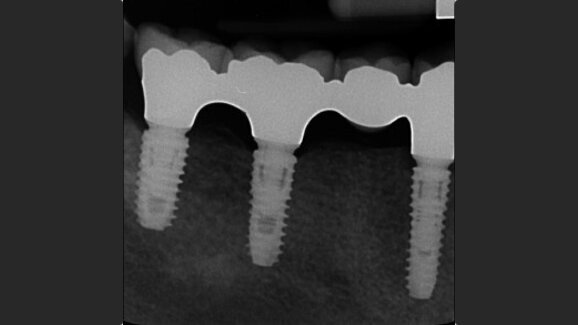

This investigation was designed as an open-cohort prospective study on completely or partially edentulous patients who received at least one bone level implant with a sandblasted and acid-etched surface and an 11° Morse taper connection. Outcome measures were the success rates of the implants and prostheses, complications, marginal bone level changes, insertion torque, implant stability quotient, bone density and soft-tissue biotype.

A total of 243 implants were placed in 90 consecutive patients and followed up for a minimum period of one year after loading (mean of 17.6 ± 2.5 months; range of 12–24 months). Five implants failed in five patients, resulting in a cumulative implant survival rate of 97.9%. Insertion torque of < 35 N cm was found to be a risk factor for implant failure (p = 0.0068). No definitive prosthesis failed, resulting in a cumulative prosthetic survival rate of 100%. Four patients experienced one technical complication each, resulting in a cumulative prosthetic success rate of 97.2%. The cumulative mean marginal bone loss between implant placement and the follow-up one year after loading was 0.37 ± 0.25 mm (95% CI: 0.26–0.30). Comparison of marginal bone loss and the investigated risk factors found statistically higher marginal bone loss for smokers, a thin gingival biotype and guided bone regeneration (p < 0.05).

Low implant failure and physiological marginal bone remodeling of 0.37 mm within one year after loading can be expected using Osstem TSIII implants in the daily practice.